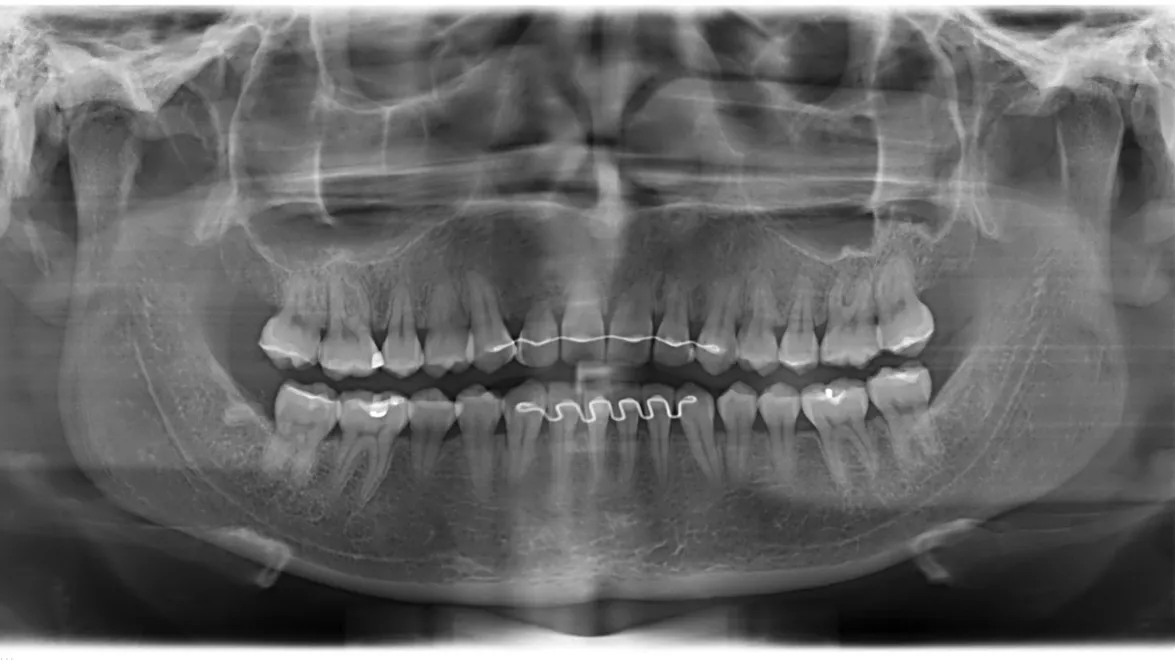

Guided rehabilitation with implant in upper incisors region, after loss due to root resorption